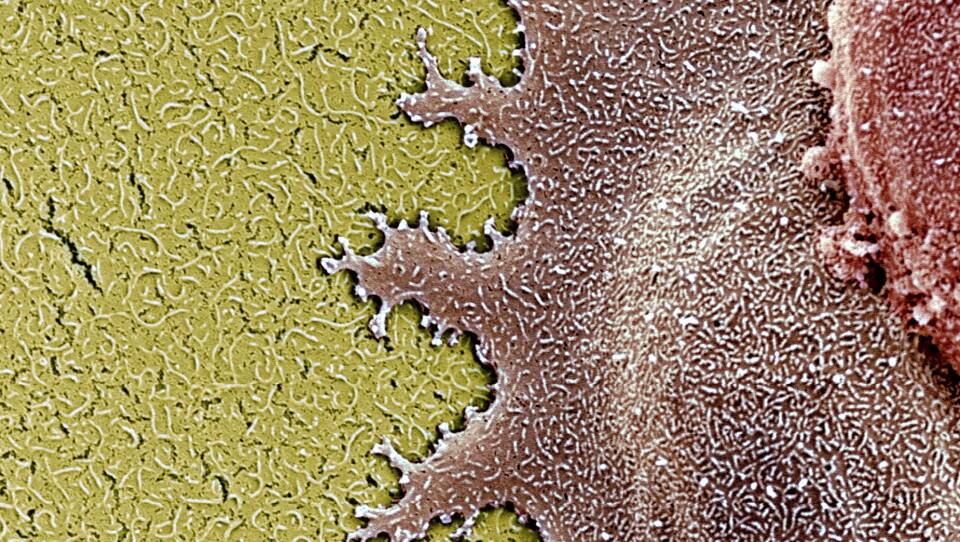

Those are the cells that were tested by the Japanese scientists. The stem cells were converted into retinal pigment epithelium (RPE) cells, which are the cells that are destroyed by macular degeneration.